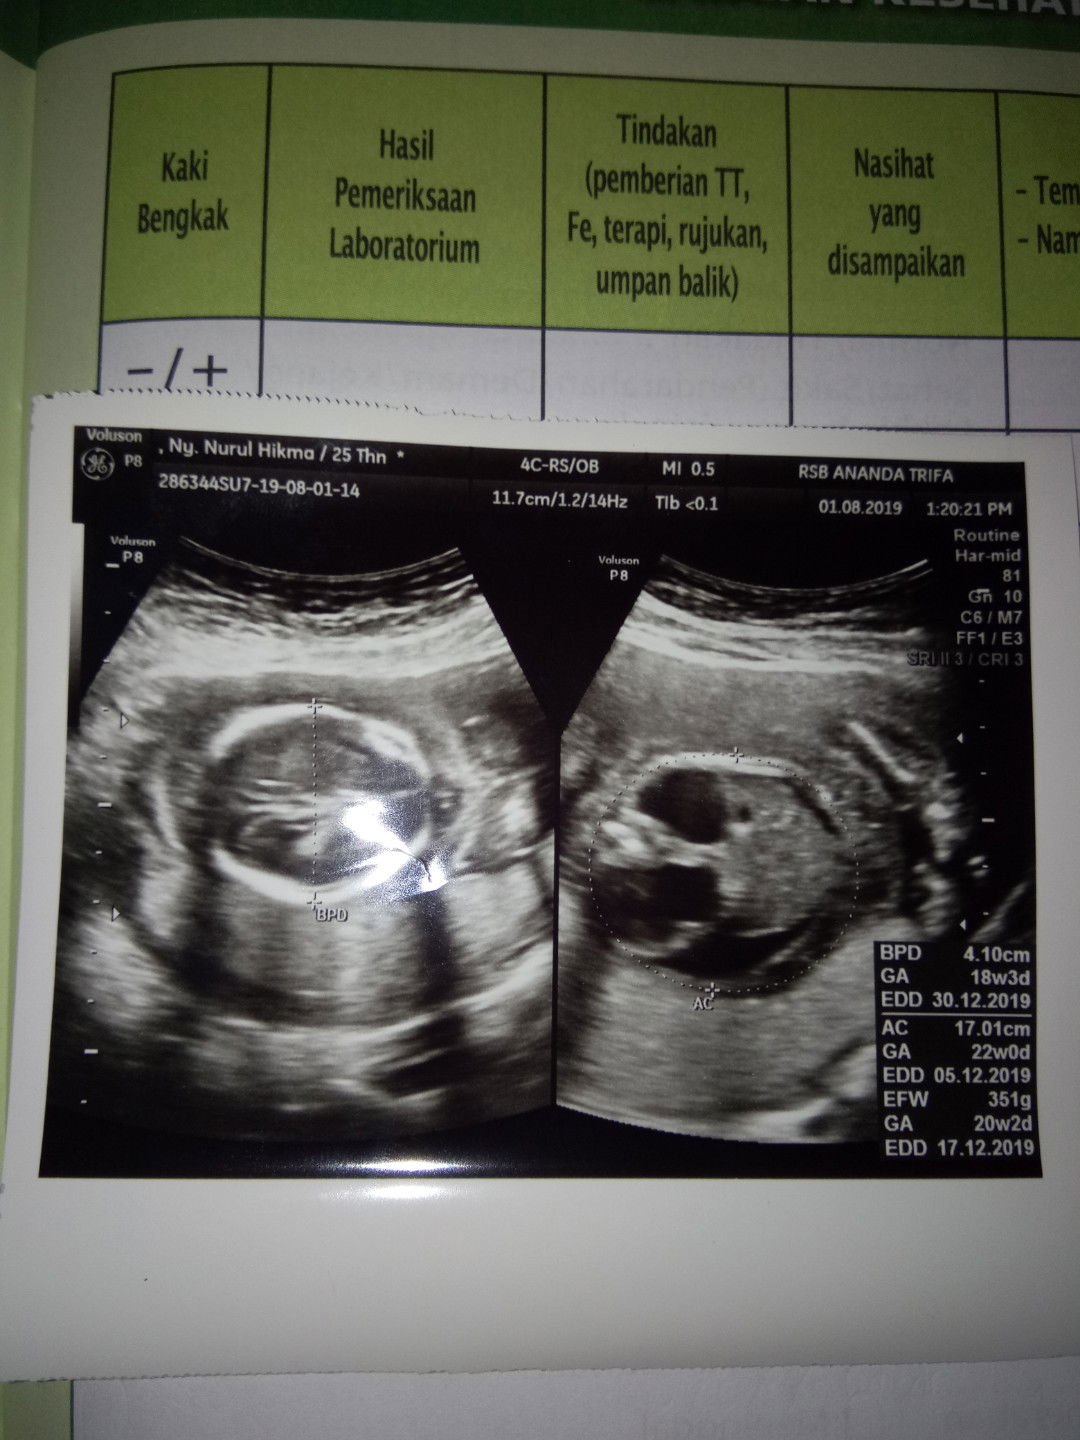

hari ini usg memasuki usia 18 minggu. awal nya periksa ke bidan, tp kata bidan denyut jantung nya terdengar lambat, tp lama kelamaan denyut debay normal, Alhamdulillah. tp ttp di kasih rujukan ke dokter SPOG krn memang lg nyeri banget perut bagian bawah, setelah sampai di dokter kemudian di USG kata dokter ada kelainan sama debay nya, kok terlihat ada 2 kantung di dalam, kantung yg 1 nya berada dalam perut bayi dan katanya perut bayi di dalam agak membesar?, tapi awal nya kata dokter ini kista, tp belum bisa di pastikan benar kista atau bukan... ya Allah semakin panik dengar nya, tp alhamdulillah detak jantung dll normal, dan ini baru pertama kali di temukan sama dokter nya... jadi nya besok di rujuk lagi ke rumah sakit umum? perut bawah udah nyeri nya minta ampun, tp ttp harus pulang pergi ke rumah sakit. kata dokter jangan panik dulu, siapa yg gak panik kalau tau ada kelainan sama calon bayi kita??? ya Allah semoga sy dan bayi dalam kandungan sehat2 saja, aamiin. dn jika bunda yg lain ada yg prnah dengar seperti kasus yg sy alami, sangat2 minta tolong untuk sharing atau masukan nya. terimakasih.